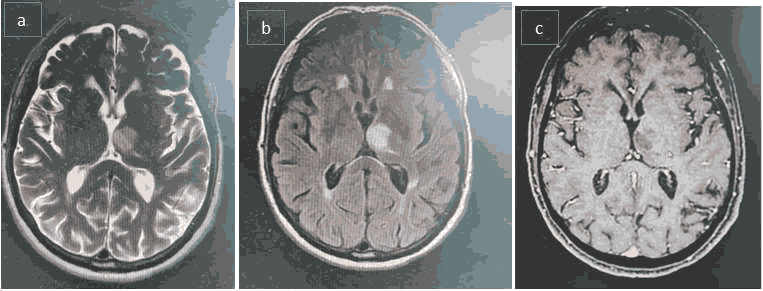

We continue the investigation with MRI BRAIN which confirms the diagnosis. A contrast MRI of brain was requested, due to atypical manifestations on the clinical chart, especially the age of presentation without a previous history of mental health problems. It showed an image suggestive of ischemic stroke in the left thalamus. (Figure 2 a-c).

Treatment with Citalopram 10 mg was initiated. Energy and mood improved slightly when the patient is seen on outpatient Department. Show ischemic stroke in the left thalamus